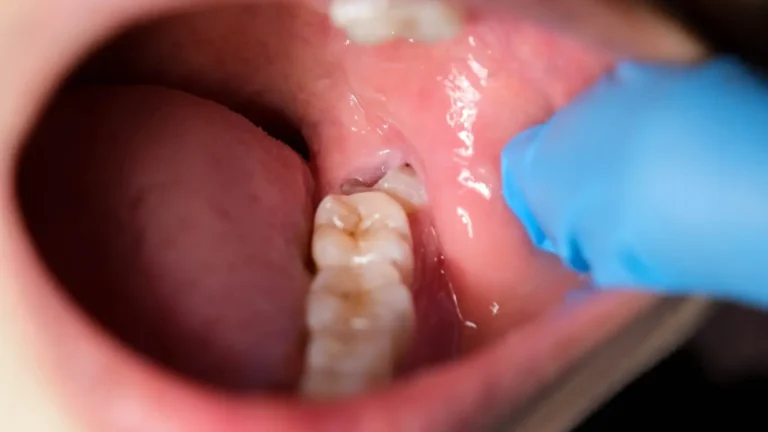

Wisdom teeth (third molars) are the last set of molars to erupt, typically between ages 17–25. Often there isn’t enough space, causing them to grow at odd angles or remain trapped beneath the gum known as “impaction”

Close-up view of a partially erupted wisdom tooth with inflamed gum tissue